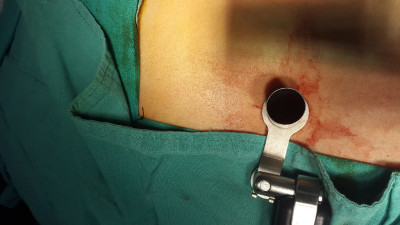

Cirugía endoscópica de columna e instrumentación

Envíado por Dr. Hugo Enrique Castro Cordero